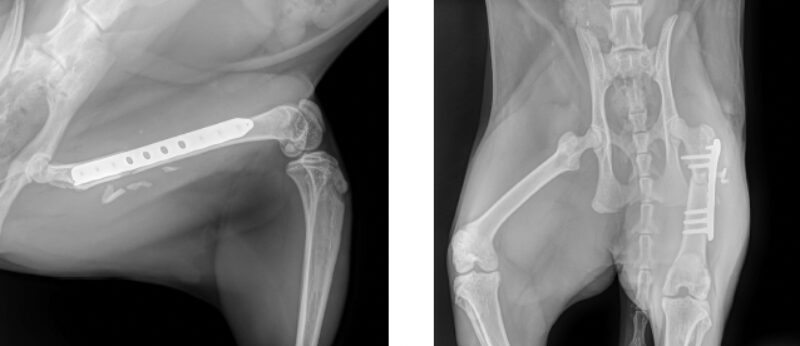

Chirurgische Versorgung der Fraktur

Im chirurgischen Konsil wurde der Entschluss gefasst, zuerst die Fraktur des Femur zu versorgen. Nach vollständiger Ausheilung dieser, wird die Gesamtsituation re-evaluiert. Besteht dann weiterhin eine vollständige oder teilweise Lähmung der rechten Vordergliedmaße, kann diese nach Bedarf in einer zweiten Operation amputiert oder das Karpalgelenk mittels Arthrodese versteift werden. Die Chirurgische Versorgung der Femurfraktur erfolgte inhouse durch Neuro- und Orthopädischen Chirurgen Marcel Sieger und sein Team. Über den kraniolateralen Zugang wurde die Trümmerfraktur mittels Überbrückungsplatte stabilisiert. Die Faszien Sub- und Intakutannaht erfolgte fortlaufend, die Hautnaht mittels Reverdin.

Physiotherapeutische Rehabilitationsmaßnahmen: Röntgenkontrolle nach 2, 6 & 12 Wochen. Die Fraktur war 8h post-OP bereits belastbar. 24h post-OP konnte die erste rehabilitationsmedizinische Einheit mit Physiotherapeutin Lea Jenhard stattfinden, im Anschluss wurde „Fussel“ nach Hause entlassen. Zustand nach 14 Tagen: Das Röntgenbild zur Kontrolle 14 Tage post-OP ergab einen zufriedenstellenden Heilungsverlauf. Die Fraktur der Hintergliedmaße wird aller Voraussicht nach komplikationslos abheilen. Die Fäden wurden gezogen, es bestand keine Wundschwellung.